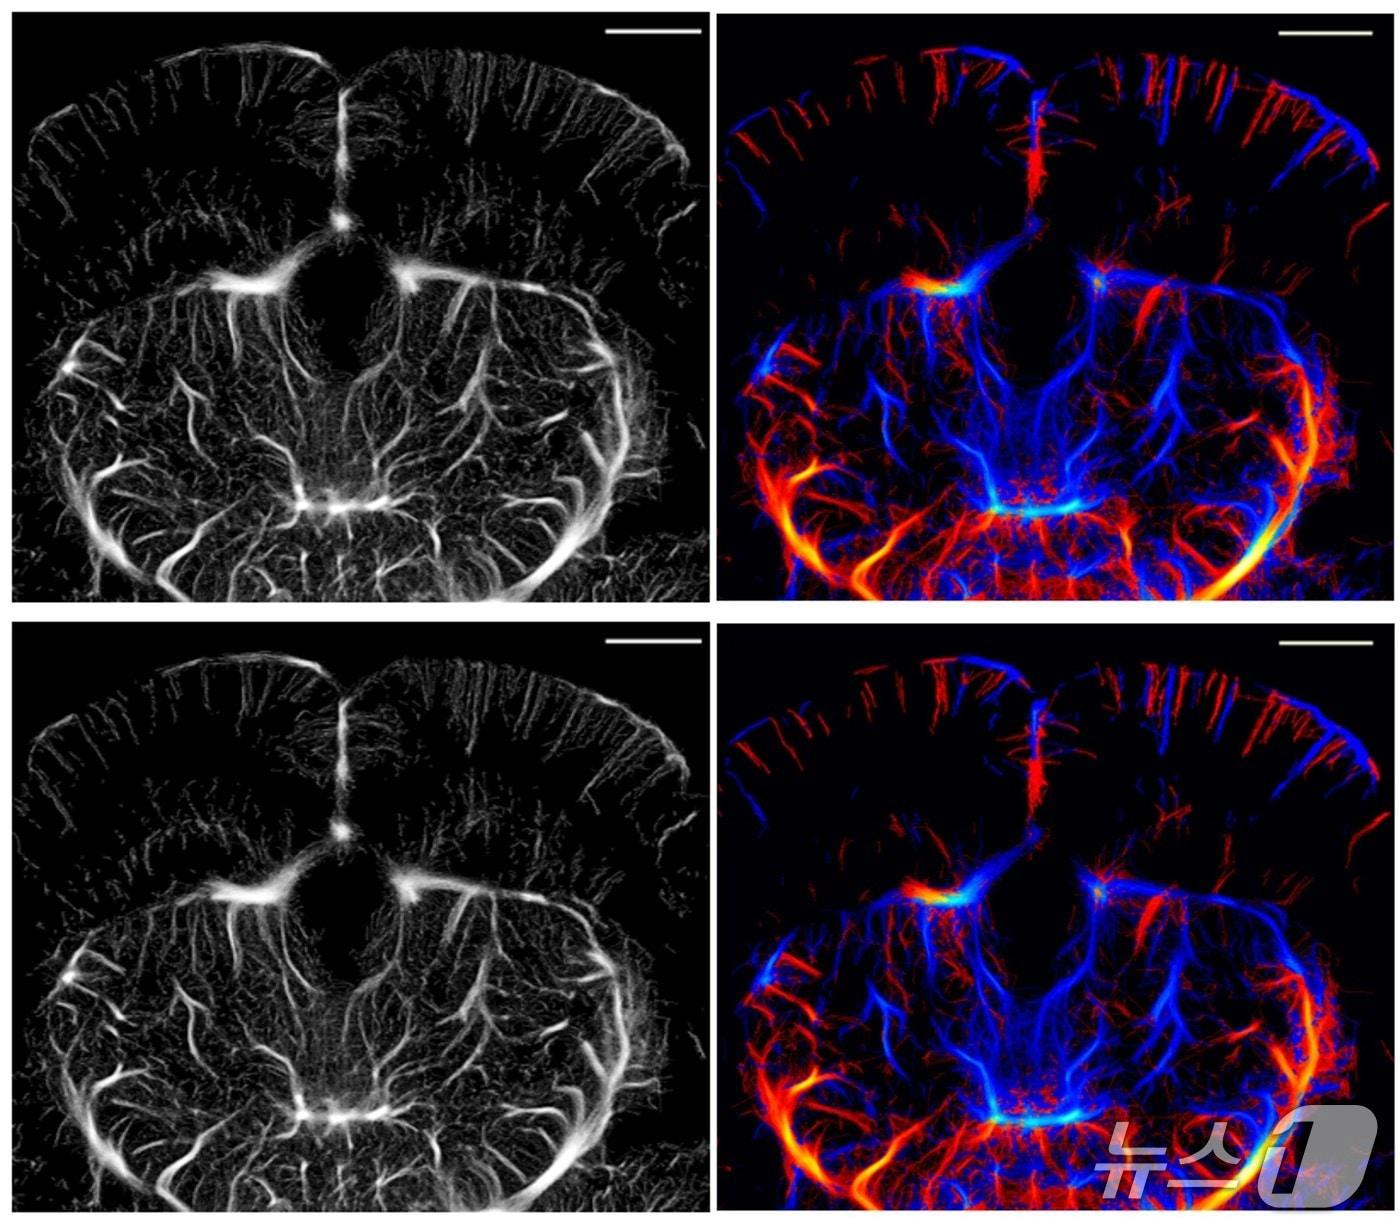

DGIST, 초음파로 뇌 속 미세혈관 보는 기술 업그레이드